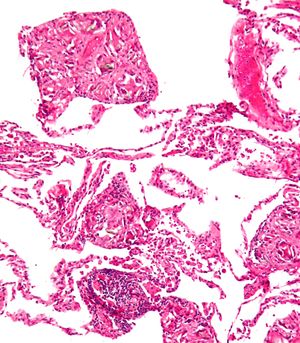

복강 내 이물질은 결국 이물 육아종에 갇히게 된다. 매우 드문 경우로, 잔류 자궁외 임신의 경우 석태아가 형성되기도 하는데, 이는 태아가 너무 커서 재흡수될 수 없고 감염으로부터 주변 조직을 보호하기 위해 석회화되는 것이다.[13]